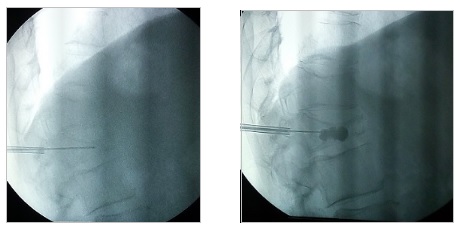

Ο αποκλεισμός του ηλιακού πλέγματος συνίσταται σε απευθείας έγχυση φαρμακευτικών ουσιών σε μία δέσμη συμπαθητικών γαγγλίων που βρίσκονται μπροστά από την αορτή και αποτελούν σταθμό μεταφοράς μηνυμάτων από τα όργανα της κοιλιάς προς το κεντρικό νευρικό σύστημα.

Ενδείκνυται σε περιπτώσεις έντονου πόνου ανθεκτικού στην φαρμακευτική αγωγή σε ασθενείς με καρκίνο παγκρέατος ή χρόνια παγκρεατίτιδα.

Με τον ασθενή σε πρηνή θέση και υπό τοπική αναισθησία, εισάγεται κάτω από ακτινοσκοπική καθοδήγηση μια βελόνα που διέρχεται από το πλάγιο τμήμα του πρώτου οσφυϊκού σπονδύλου, το άκρο της οποίας στην τελική του θέση φθάνει στην περιοχή ακριβώς μπροστά από την αορτή. Γίνεται έγχυση σκιαγραφικού για απεικόνιση του πλέγματος και αμέσως μετά δίνεται το τοπικό αναισθητικό και η κορτιζόνη. Μέσω της διαδικασίας αυτής μπορούν να εγχυθούν και νευρολυτικοί παράγοντες, όπως η αλκοόλη και η φαινόλη, οι οποίοι έχουν καταστροφική δράση. Το block με τοπικό αναισθητικό και κορτιζόνη έχει δράση για λίγες μέρες. Όσοι ασθενείς ανταποκριθούν θετικά, μπορούν να υποβληθούν σε δεύτερο χρόνο σε νευρόλυση με χρήση ραδιοσυχνοτήτων, η οποία προσφέρει μακρά θεραπευτική δράση.